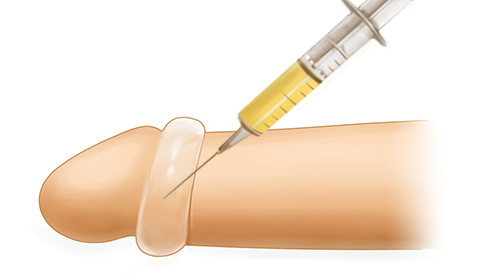

진피분말

유로진의 진피분말은 대체진피를

분말화하여 피부절개 없이

주사를 이용한 확대로

진피와 필러의 장점을 동시에 느껴볼 수 있습니다

-

특 - 징

- 피부절개가 없는 비수술 확대

- 10여분 정도의 짧은 시술 진행

- 진피를 분말화한 재료로 긴 확대 지속기간

필 러

유로진은 액상형태인 필러 특성상 시술시 형태가

매우 중요하므로

상·중·하 피하층에 골고루

동시 주입하여 자연스러움과 확대효과를 높입니다

-

특 - 징

- 피부절개가 없는 비수술 확대

- 10여분 정도의 짧은 시술 진행

- 흉터 및 회복기간에 대한 부담이 거의 없음

자가지방

유로진은 지방 속 수분·혈액을 걸러주는

압축·정제과정을 통해

순수지방만을

사용하여 확대 지속효과를 높였습니다